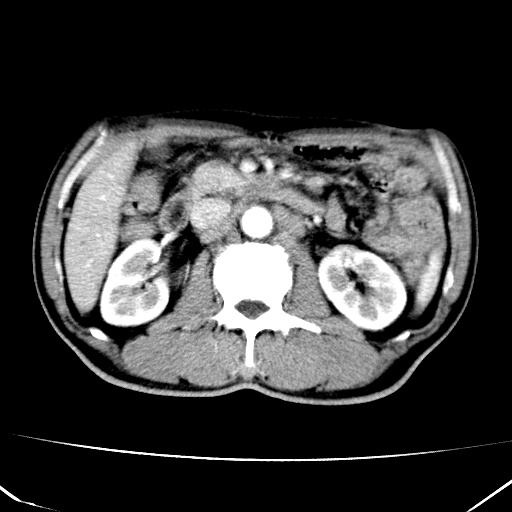

标题: CT17975:请求会诊。男、57岁。上腹部胀痛2天。临床诊断:糜 [打印本页]

标题: CT17975:请求会诊。男、57岁。上腹部胀痛2天。临床诊断:糜

肝脏多发类圆形低密度影,考虑肝脏转移瘤,肝胃韧带一淋巴结肿大,原发?胃癌?

考虑胃癌并肝脏及腹膜后淋巴结转移;不排除淋巴瘤。

肝内转移瘤,腹腔及腹膜后淋巴结转移。